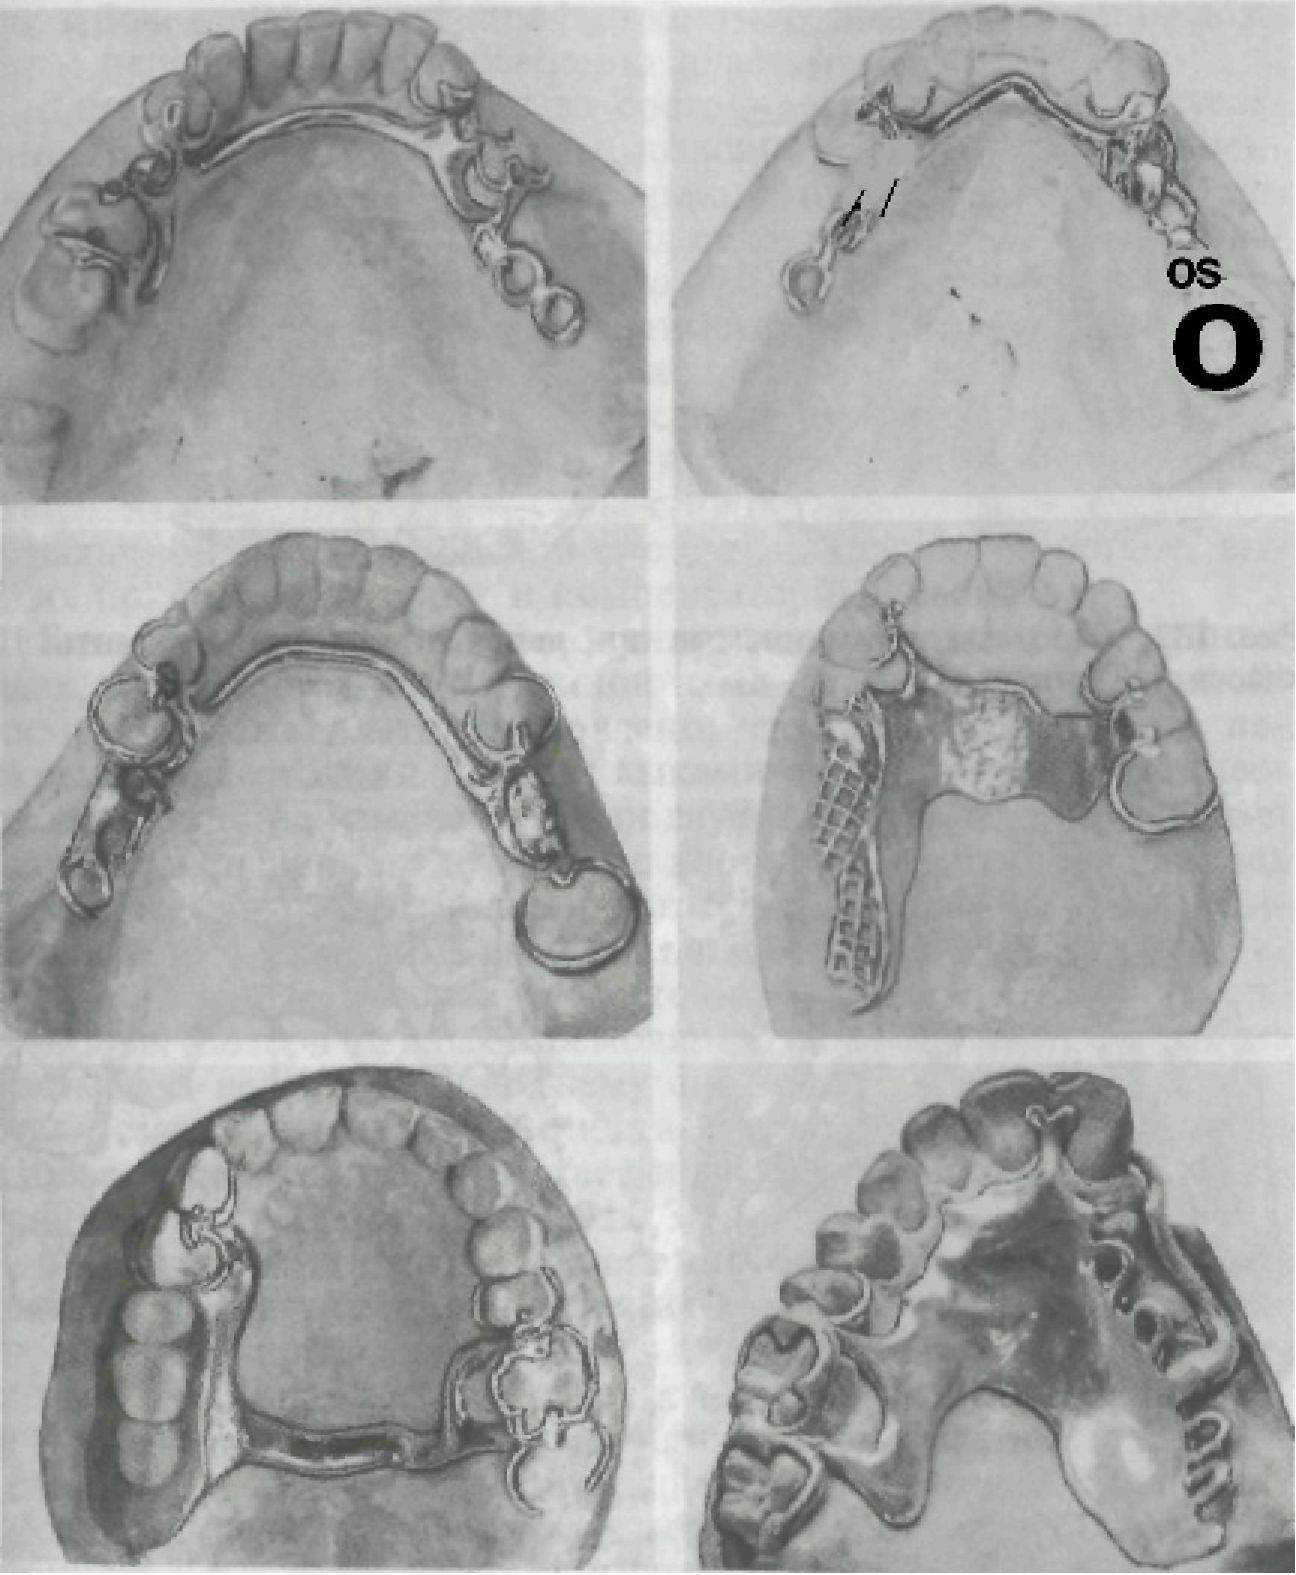

На рис. 131—133 представлены варианты дефектов зубных рядов, варианты врачебных решений по выбору конструкций съемных протезов. Схемы на рисунках позволят студенту самостоятельно осмыслить обоснование выбора конструкции съемного протеза.

Рис. 132. Протезы, применяемые при лечении адентий. Варианты III класса по Кенеди.